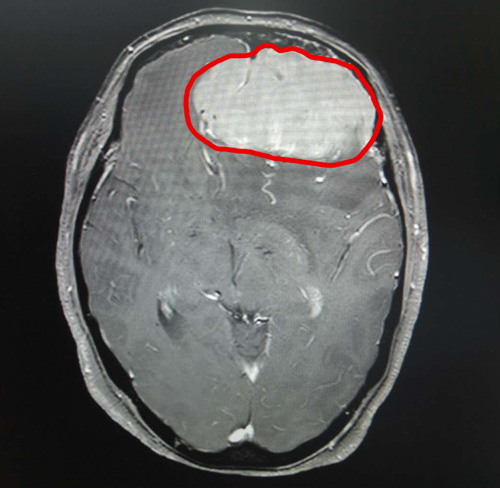

头颅MRI增强显示,丁阿姨的前颅窝有巨大的团块状异常信号。肿瘤大小约为6.9×5.6×5.4厘米,其大小与鸭蛋接近。

头颅MRI影像清晰显示了巨大的脑膜瘤